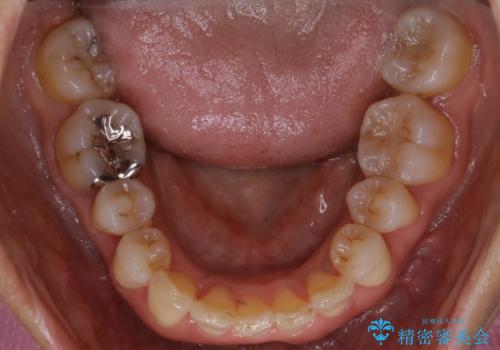

- 上下の歯のがたつきと、噛み合わせが深いことを気にされてご相談にいらした方です。噛み合わせに参加していない歯を抜歯してインビザラインにて治療を行いました。

一般的に噛み合わせの深い方へのインビザライン治療は適応が難しいとされていますが、今回は噛む力を上手にコントロールできたことと、内側に入り込んでいた前歯の角度を調整したことで下の歯がしっかり見えるようになりました。短期間で劇的に見た目が改善し、大変喜んでいただけました。